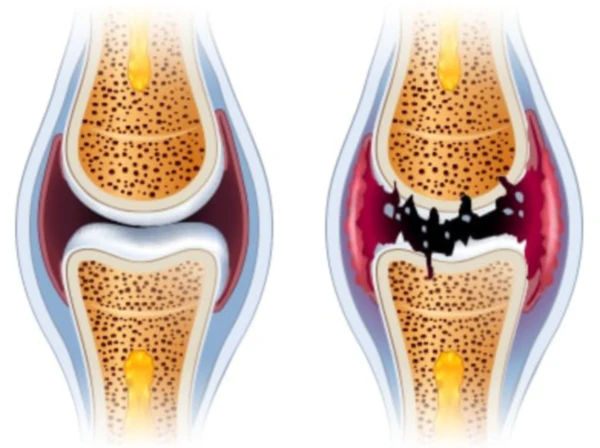

통풍은 주로 체내에 과다 축적된 요산으로 인해 발생합니다. 요산은 우리가 섭취하는 다양한 음식이 소화되어 최종적으로 대사된 후 혈액에 녹아 있다가 소변으로 배출되는 물질입니다. 일반적으로 혈액 내에서 요산은 정상 수준을 유지하며 배설됩니다. 그러나 통풍 환자는 혈액 내 요산이 과다하게 증가합니다. 이러한 과다 축적된 요산은 결정체로 변화하고, 이러한 결정체가 관절 내에 침착하여 염증을 일으킵니다.

통풍을 적절히 치료하지 않을 경우, 발작성 관절염의 빈도가 증가하고 침범하는 관절 수도 더 많아지며, 회복에 필요한 시간도 증가합니다. 반복적인 관절염은 관절을 점차 손상시키며, 만성적인 관절염으로 진행될 수 있습니다. 또한 통풍성 결절이라 불리는 덩어리가 관절 주위나 피부 조직에 나타날 수 있습니다. 이러한 결절은 요산 결정체의 덩어리로 어느 부분에서든 형성될 수 있으며, 주로 팔꿈치, 귀, 손가락, 발가락, 발목 등에서 발생할 수 있습니다. 때로는 요로 결석을 형성하기도 합니다.